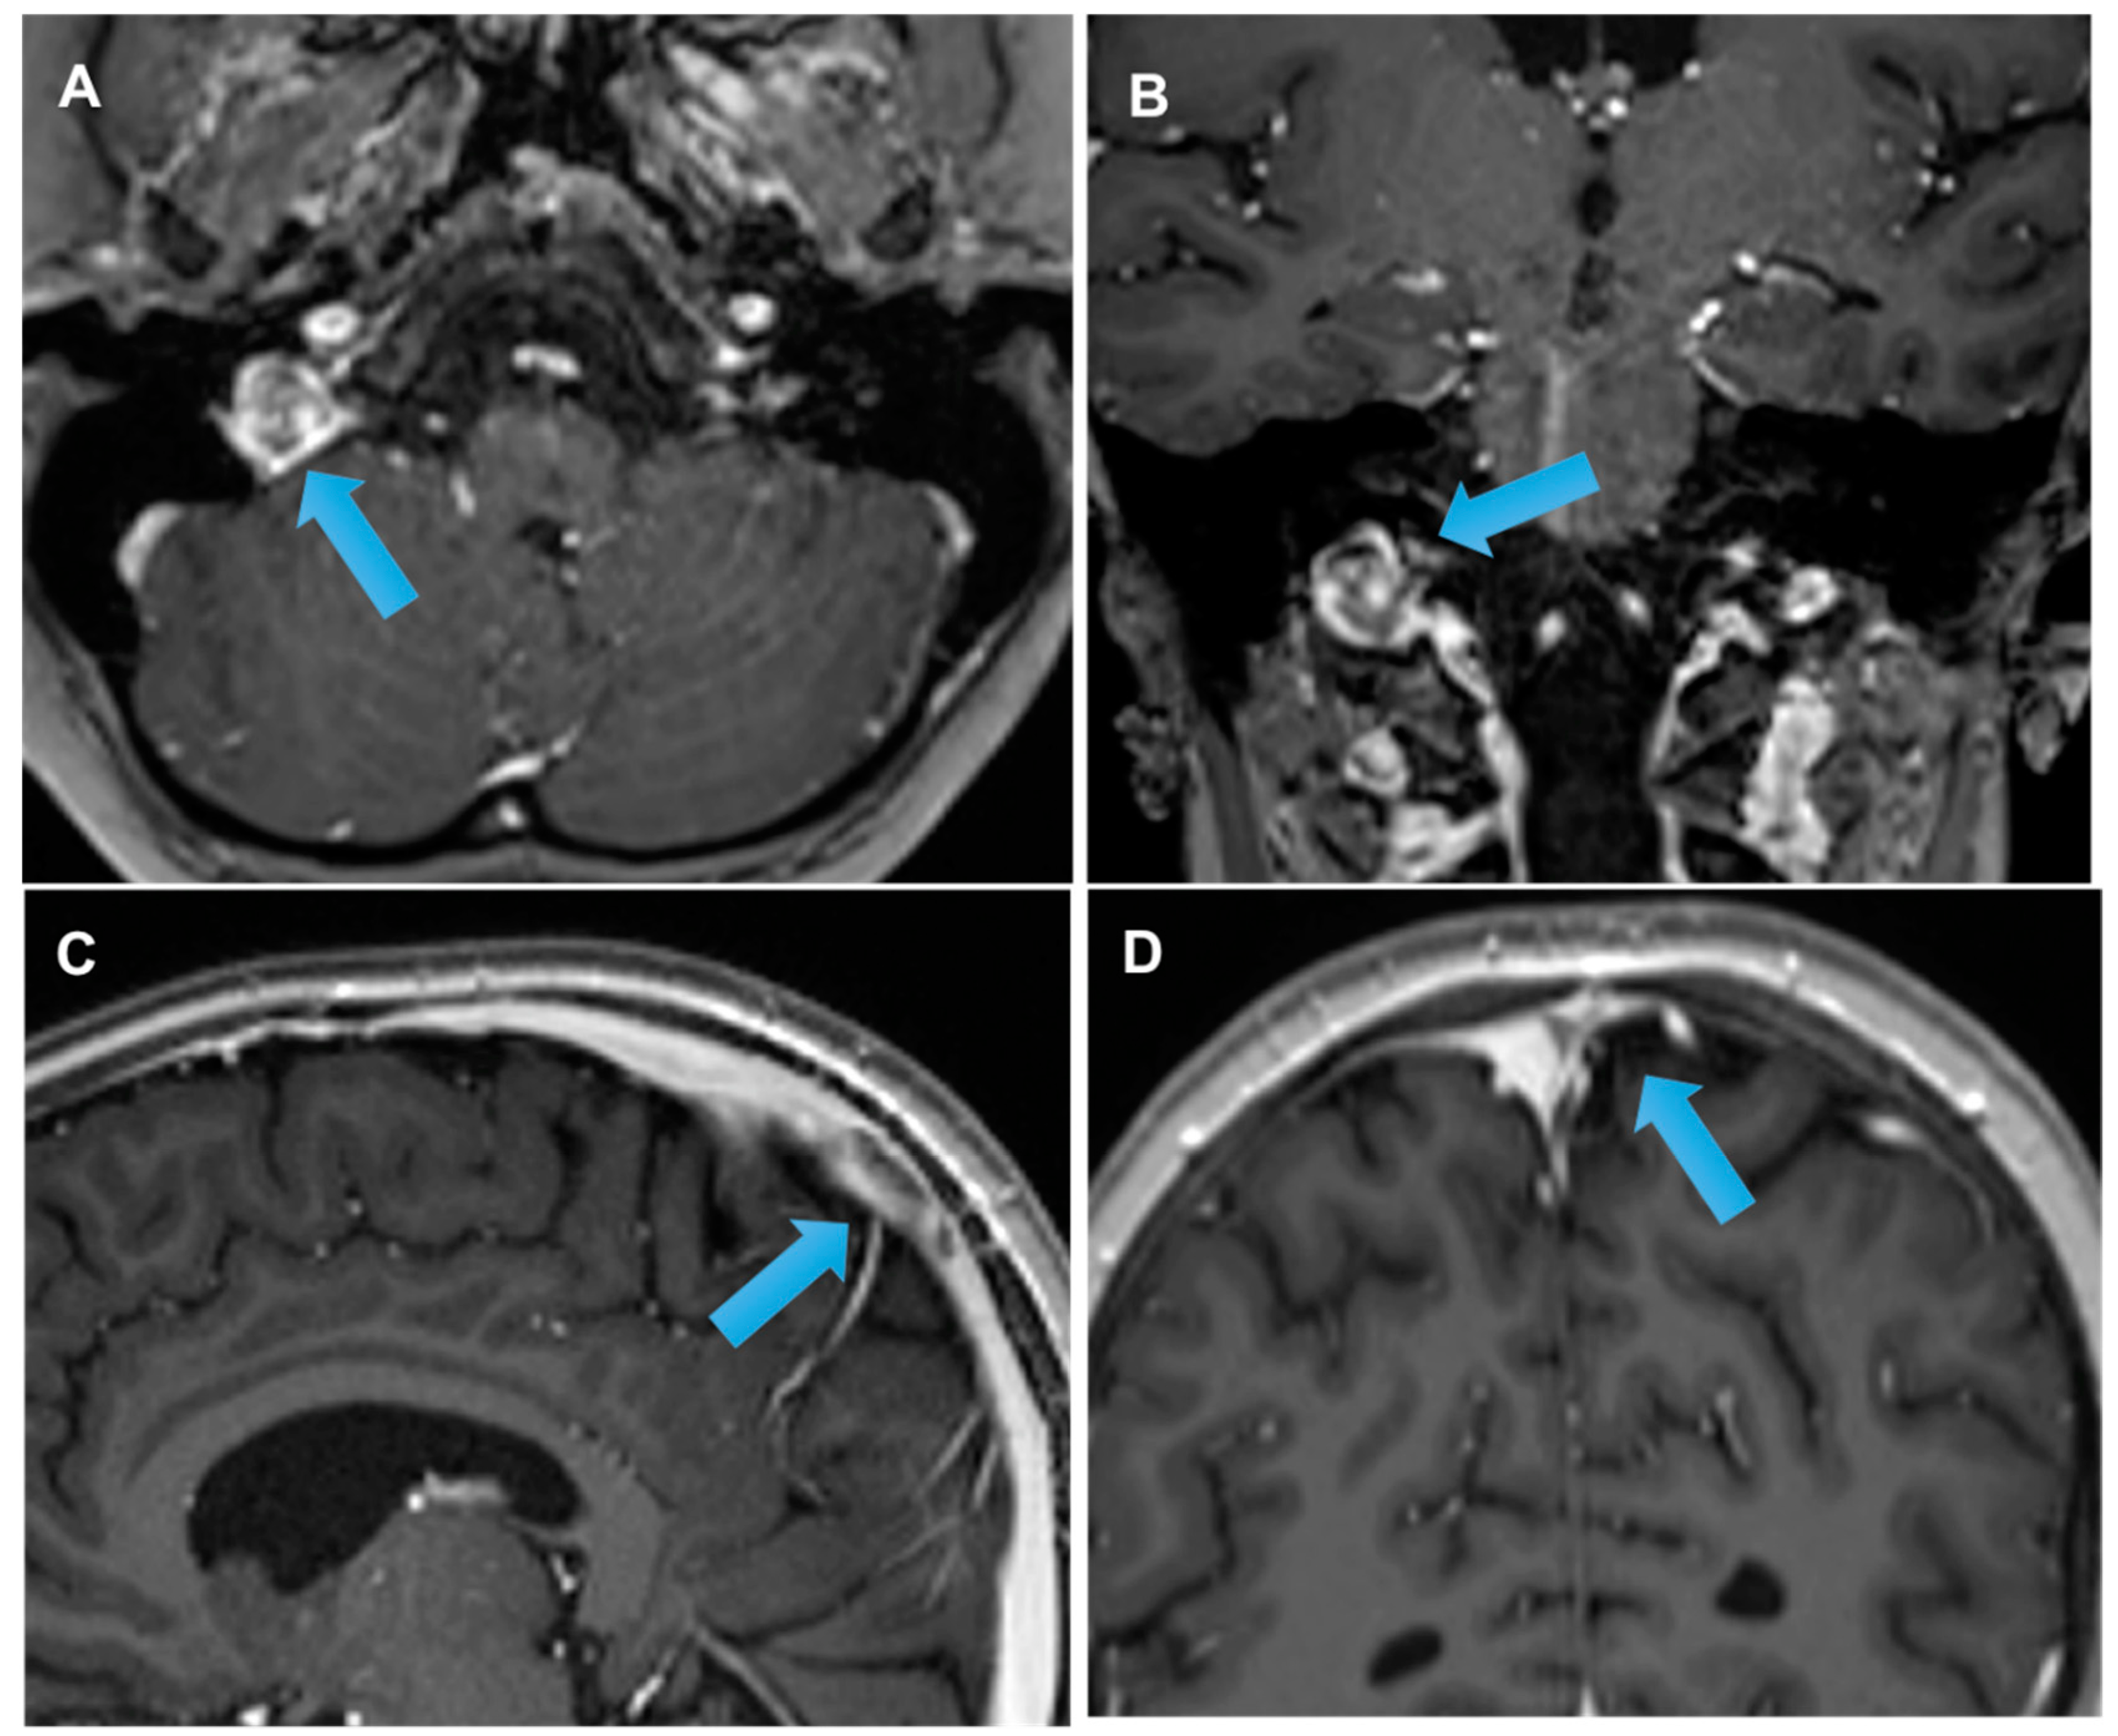

3.4. Acute Late-Onset Encephalopathy after Radiotherapy (ALERT Syndrome)

- Di Stefano, A.L.; Berzero, G.; Vitali, P.; Galimberti, C.A.; Ducray, F.; Ceroni, M.; Bastianello, S.; Colombo, A.A.; Simoncelli, A.; Brunelli, M.C.; et al. Acute late-onset encephalopathy after radiotherapy: An unusual life-threatening complication. Neurology 2013, 81, 1014–1017. [Google Scholar] [CrossRef] [PubMed]

3.6. Radiation-Induced Cerebrovascular Disease

- Brada, M.; Ashley, S.; Ford, D.; Traish, D.; Burchell, L.; Rajan, B. Cerebrovascular mortality in patients with pituitary adenoma: Cerebrovascular Mortality in Patients with Pituitary Adenoma. Clin. Endocrinol. 2002, 57, 713–717. [Google Scholar] [CrossRef] [PubMed]

- Roongpiboonsopit, D.; Kuijf, H.J.; Charidimou, A.; Xiong, L.; Vashkevich, A.; Martinez-Ramirez, S.; Shih, H.A.; Gill, C.M.; Viswanathan, A.; Dietrich, J. Evolution of cerebral microbleeds after cranial irradiation in medulloblastoma patients. Neurology 2017, 88, 789–796. [Google Scholar] [CrossRef] [Green Version]

- Murphy, E.S.; Xie, H.; Merchant, T.E.; Yu, J.S.; Chao, S.T.; Suh, J.H. Review of cranial radiotherapy-induced vasculopathy. J. Neuro-Oncol. 2015, 122, 421–429. [Google Scholar] [CrossRef]

- Bavle, A.; Srinivasan, A.; Choudhry, F.; Anderson, M.; Confer, M.; Simpson, H.; Gavula, T.; Thompson, J.S.; Clifton, S.; Gross, N.L.; et al. Systematic review of the incidence and risk factors for cerebral vasculopathy and stroke after cranial proton and photon radiation for childhood brain tumors. Neuro-Oncol. Pract. 2021, 8, 31–39. [Google Scholar] [CrossRef]